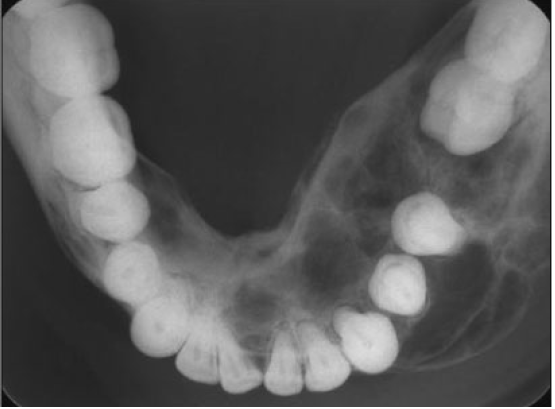

central giant cell granuloma occlusal radiograph of mandible

may demonstrate CGCG as cause of expansion of internal and external cortical bones